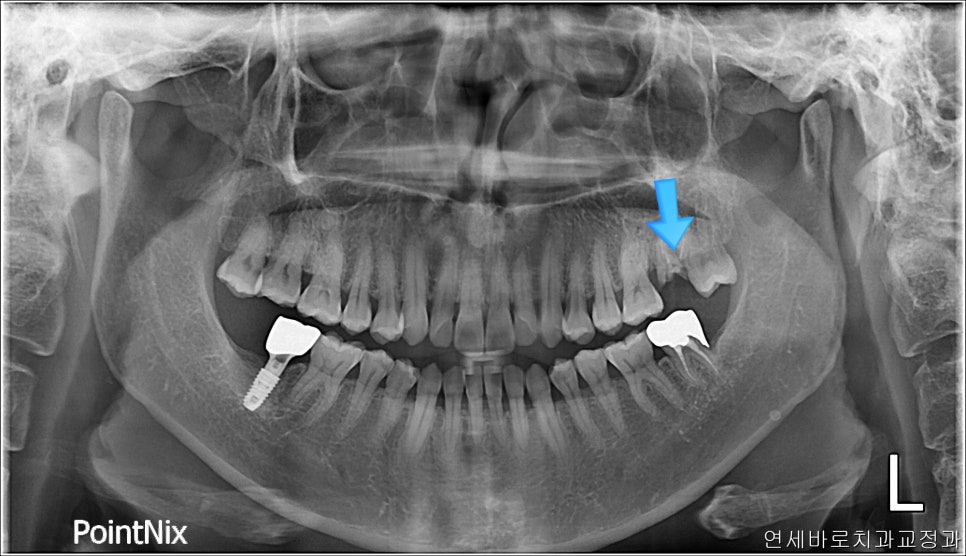

미니스크류를 사진에는 하나만 보이지만 두개 심었고,

계속 당겼습니다

3차원적인 이동을 하다보니 오래 걸렸어요

중간에 몇달은 움직임이 없이 멈춰있기도 하고.